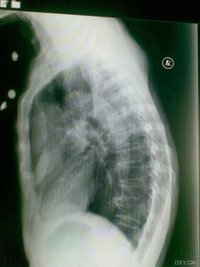

2.X線檢查:是診斷肺癌的一個重要方法,中央型肺癌肺平片可見到肺門部位有不規則的半圓形陰影。周圍型肺癌的X片上,肺野中有直徑1~2厘米的結節到5~6厘米的巨大塊狀陰影。

X線表現

②癌瘤致支氣管狹窄,可出現一側或葉的肺氣腫。深呼氣位照片易於顯示。

③癌瘤致支氣管狹窄,造成分泌物引流不暢,則出現阻塞性肺炎或阻塞性肺不張。

④癌瘤致支氣管阻塞則出現阻塞性肺不張。另外,癌瘤向支氣管外蔓延,形成肺門區腫塊。右上葉肺癌可出現典型的橫“S”征。